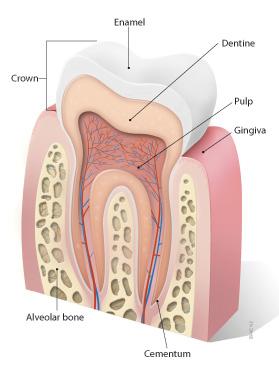

10

11

12

13

baby teeth

Permanent Teeth

Incisors (8)

16

Permanent Teeth

Premolars (8)

18

Permanent Teeth

Crown

Neck

Root

Alveoli

Gingiva

Enamel

Dentin

Cementum